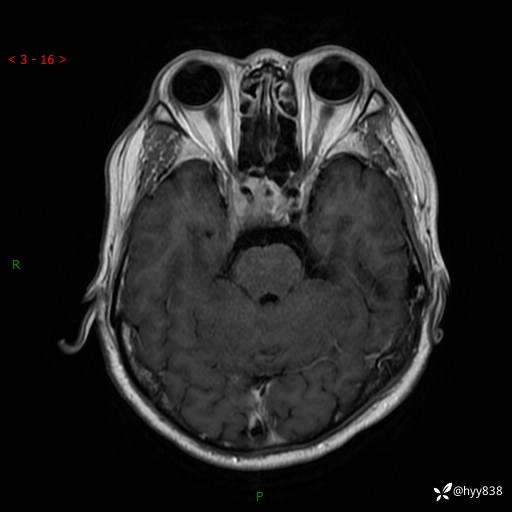

MRI增强(外院平扫)